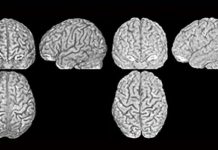

Research: Every person has a unique brain anatomy —

Like with fingerprints, no two people have the same brain anatomy, a study by researchers of the University of Zurich has shown. This...